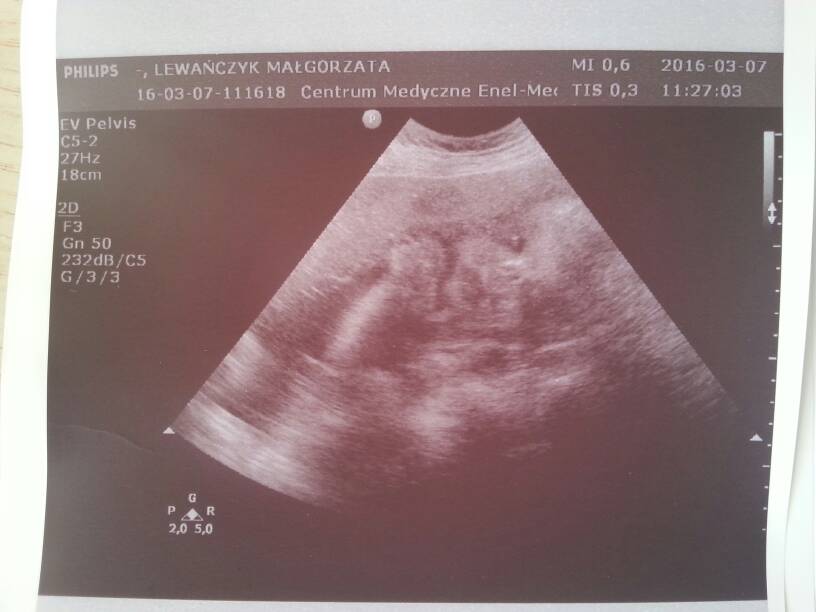

Mój synek. Ślicznie się do zdjęcia ustawił :)

Załączniki

• 1457439671425.jpg

1457439671425.jpg

36,5 KB · Wyświetleń: 141